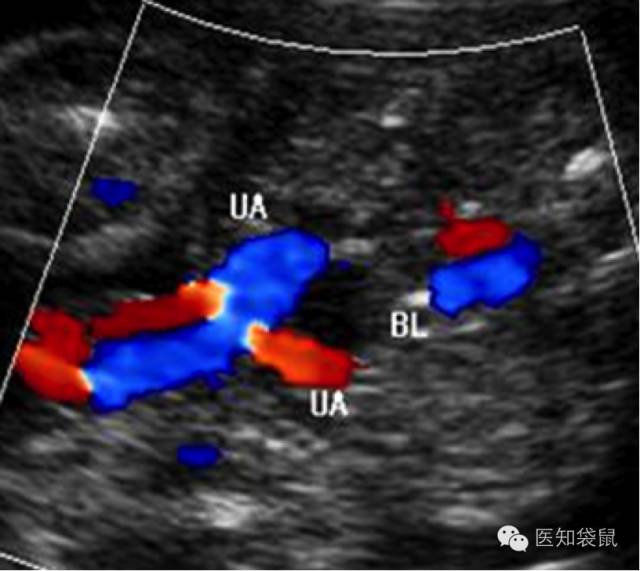

彩色B超诞生于上世纪80年代,图像以红蓝两色为主,并不是大众认为的彩超就像彩色电视机一样。

彩超通常是用来查看血液的流动方向,迎面而来的显示为红色,往远处去的显示为蓝色。因此,红色≠动脉,蓝色≠静脉。